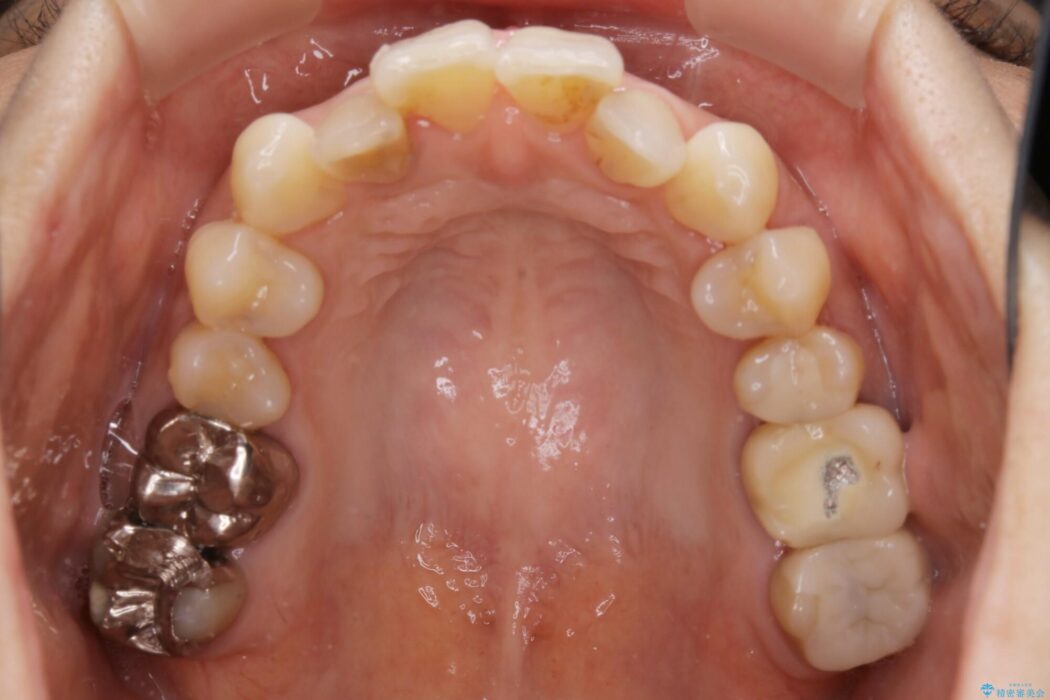

全体的に歯列が狭窄しており、本来外側に覆いかぶさっている上の前歯が内側に入り込んでいました。

歯列弓全体の形状を整えるとともに歯の大きさもコントロールすることで非抜歯にて矯正を行いました。

歯並びが悪くなる原因の一つに「歯列弓の狭窄」というものがあります。

奥歯や前歯が内側(舌側)に倒れ込んでしまったり、歯が生えてくる位置が内側になってしまうことにより歯並びのアーチが狭くなってしまうことを言います。

このような場合、歯並びのアーチを拡大してあげるだけでもガタつきを無くすためのスペースがかなり作れることがあります。